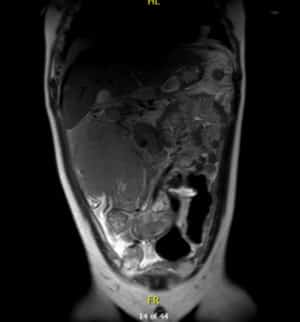

Resonancia magnética

Por su parte, en la resonancia magnética se observa una masa voluminosa infiltrativa en flanco derecho que mide 140 x 120 x150 mm, íntima relación con área ileocecal y colon ascendente al que rodea en su totalidad sin condicionar obstrucción.

Estas pruebas hacían pensar en un linfoma de Burkitt.